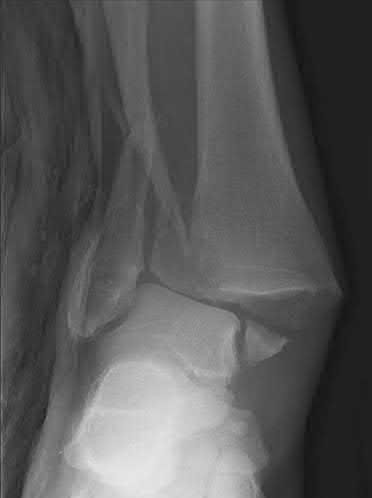

A 34-year-old male sustains the closed injury seen in Figure A as a result of a high-speed motor vehicle collision. What is the most appropriate next step in treatment?

The radiograph shows a comminuted pilon fracture, which is associated with high-energy trauma and significant soft tissue injury. The tested concept here is the importance of avoiding definitive reduction and fixation of this high-energy injury, which has been shown to be associated with an increased risk of wound complications and deep infections (as compared to staged treatment with usage of a spanning external fixator).

Patterson et al. reviewed 23 consecutive patients with comminuted distal tibia fractures. They showed 0% infections or wound-healing problems in their patient population treated with a two-staged protocol. Their protocol involved fibula fixation with an intramedullary implant and application of a medial external fixator to to regain length and restore anatomic alignment. Reevaluation of the limb occurred ten to fourteen days later for definitive fixation.

Sirkin et al. retrospectively reviewed 40 closed and 17 open pilon fractures (AO types 43A-C) that were treated with staged surgical management (avg. time from ext. fix. to formal reconstruction was 14 days (range 4 to 31) They reported 17% post-operative wound complication in the closed group and 11% post-operative wound complication in the open group (Gustilo Type I-III). They suggest the technique was successful in both closed and open pilon fractures.